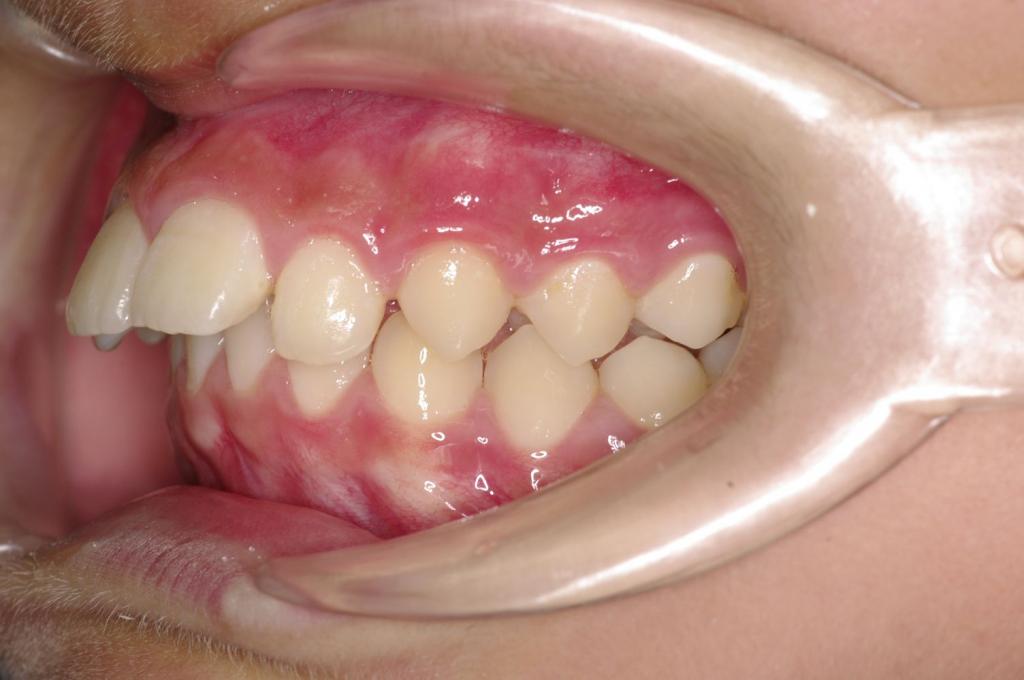

前歯、出っ歯・開咬の矯正治療

(治療期間、治療前後写真、治療方法、費用)WORKS